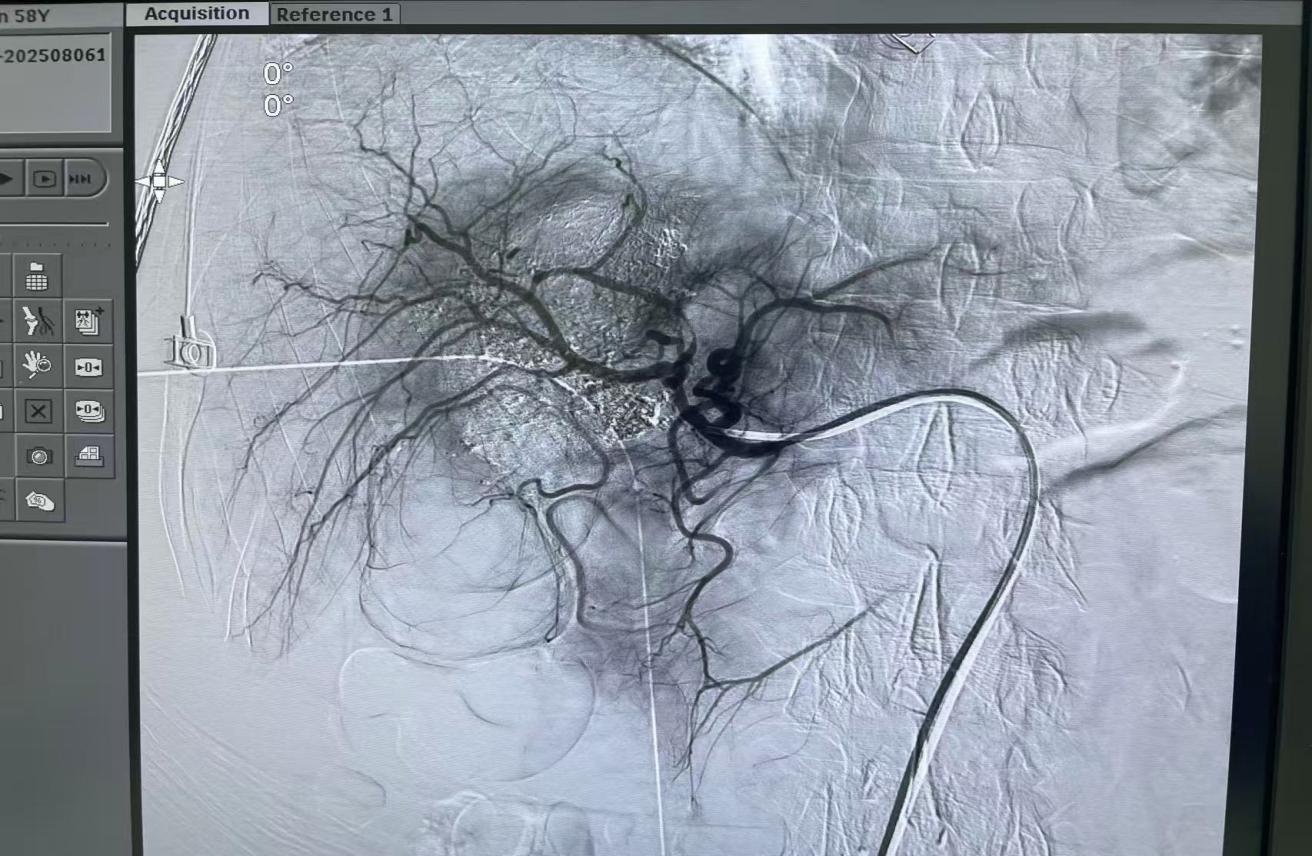

圖3:患者DSA造影,黃色箭頭處為新發(fā)病灶。